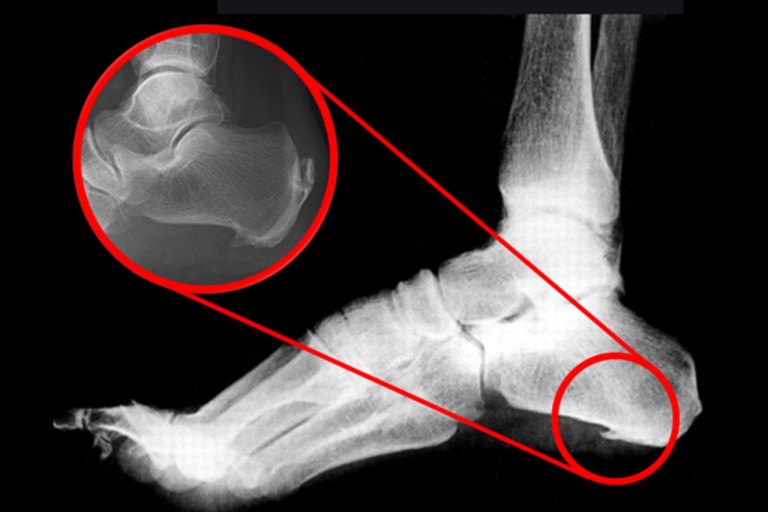

발바닥통증의 원인 고통성 족부 변형 (뼈 돌출 등)

- 발바닥의 뼈나 관절의 이상으로 인해 통증이 발생할 수 있습니다. 뼈의 돌출이나 과도한 뼈 성장(예: 발가락의 뼈가 튀어나오는 경우) 등이 그 예입니다. 이 경우 신발이 맞지 않거나 발에 가해지는 압력이 증가하여 통증이 유발됩니다.